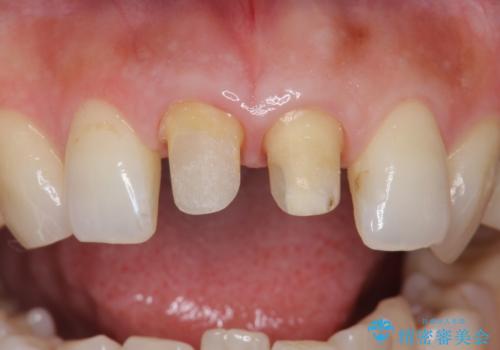

- 前歯の変色を主訴に来院されました。

変色に対してはかぶせ物で周囲の歯との色調を合わせます。

根管治療についてご説明をし、右上の1本だけ再根管治療を行うこととなりました。

- 右上1/再根管治療66,000円+ファイバーコア22,000円+仮歯11,000円+ジルコニアクラウン(スタンダード):121,000円 左上1/仮歯11,000円+ジルコニアクラウン(スタンダード)121,000円 合計352,000円(税込)費用は治療当時の料金となります

先端に透明感のあるかぶせ物を装着することで審美的な問題を解決しつつ、少しガタついていた歯並びも改善することができました。